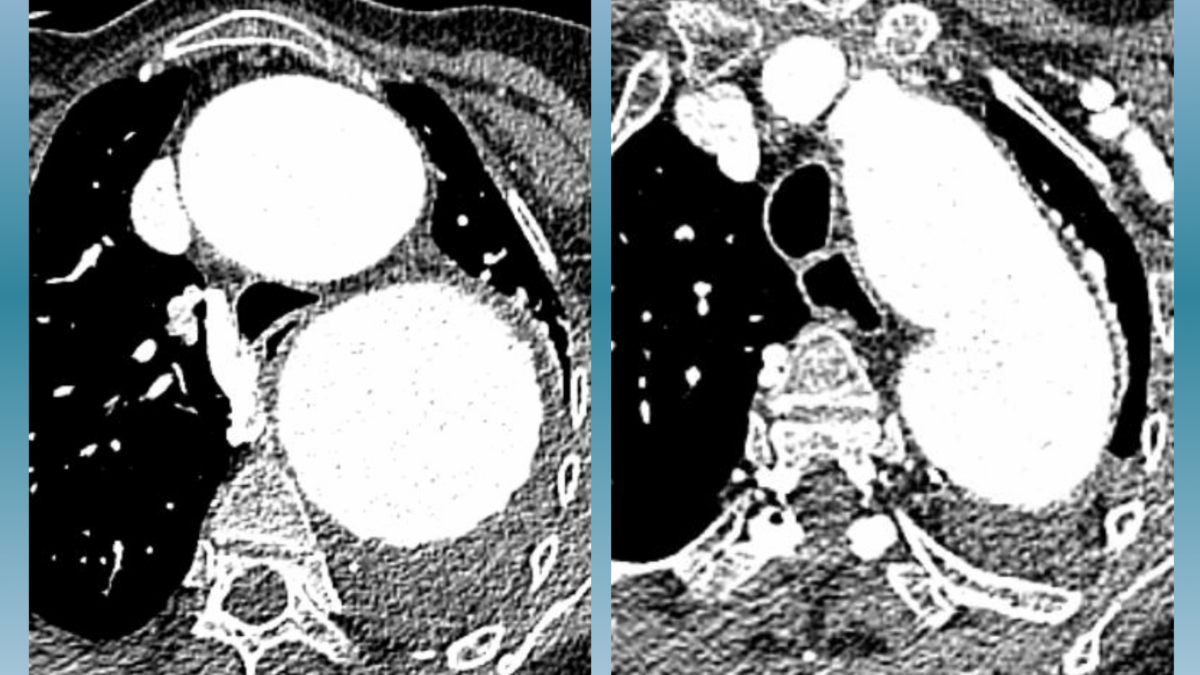

mars 5, 2025Ce cas clinique met en lumière l’aggravation progressive d’une difficulté respiratoire chez un patient fragilisé par des infections respiratoires chroniques, un état de faiblesse générale et la présence d’un important anévrisme de l’aorte thoracique, pour lequel une intervention chirurgicale avait été écartée en 2022. »

anevrisme aorte et compression bronchique